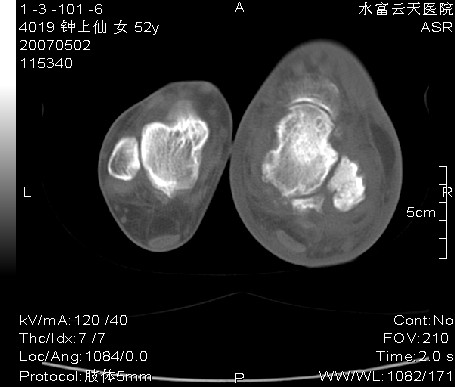

右足跗骨关节面毛糙,滑膜下多发虫蚀状破坏区,周围有硬化边,软组织肿胀明显,首先考虑关节结核;结合实验室检查及平片排除创伤性关节炎合并化脓性感染。

右足跗骨关节面毛糙,滑膜下多发虫蚀状破坏区,并形成空洞及见空洞内死骨,周围有硬化边,软组织肿胀明显,支持首先考虑:右足跗骨结核。

右跟骨轻度膨胀,轮廓不规则,见明显增生硬化,且见斑片状骨破坏及小死骨形成,有软组织肿胀明显,皮下脂肪密度增高。考虑右跟骨陈旧性骨折,右跟骨化脓性骨髓炎

右足跗骨关节面毛糙,滑膜下多发虫蚀状破坏区,并形成空洞及见空洞内死骨,周围有硬化边,软组织肿胀明显,支持首先考虑:1:右糖尿病足,查血糖.2右足骨髓炎

右足跗骨关节面毛糙,滑膜下多发虫蚀状破坏区,周围有硬化边,软组织肿胀明显,首先考虑创伤性关节炎合并化脓性感染;结关节结核合实验室检查及平片排除。